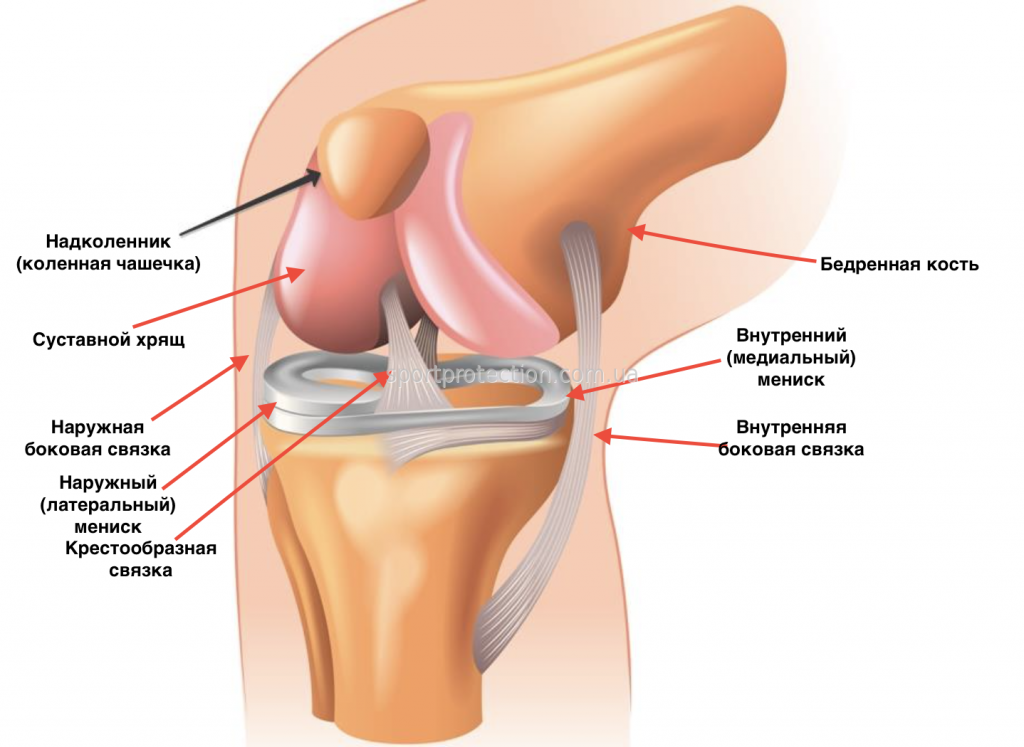

Анатомические изображения менисков и коленного сустава

Раздел: Иллюстрированные советы